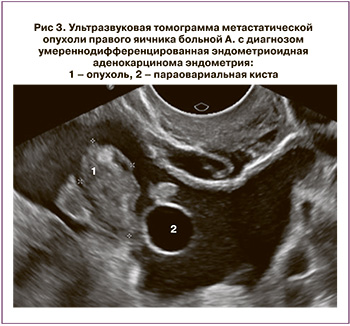

При УЗИ: Печень без очаговых изменений. Большой сальник утолщен, бугристый, метастатически изменен, толщиной 2,2–2,5 см. Матка увеличена, размеры тела 8,0×6,0×8,5 см, контур ровный, с остаточными признаками аденомиоза, из-за которого граница эндометрия отчетливо не визуализируется. В нижней трети тела и просвете цервикального канала определяются солидные структуры толщиной до 2,0 см, нижний полюс которых визуализируется на 1,5 см выше уровня наружного маточного зева. По левому ребру шейки матки определяется образование диаметром 5,0 см (УЗ-картина соответствует шеечной миоме). Над маткой слева определяется солидно-кистозное образование с четкими неровными контурами, размерами 20,0×18,0 см, в его структуре определяются перегородки и кистозные полости, в которых визуализируются множественные солидные сосочковые структуры, в перегородках и сосочковых структурах определяются локусы патологического кровотока при ЦДК и ЭД (рис. 2). Правый яичник не увеличен, солидной неоднородной структуры, с четкими неровными контурами, размерами 2,2×1,2 см, с единичными локусами патологического кровотока при ЦДК и ЭД (рис. 3), рядом определяется параовариальная киста диаметром 2,0 см. Выявлена свободная жидкость в области малого таза (+3,6 см). Заключение: Опухоль яичников (сложно дифференцировать между первичной опухолью и метастатической). Опухоль матки (следует дифференцировать между опухолью цервикального канала и тела матки). Метастазы в большом сальнике. Асцит. Нельзя исключить первично-множественную опухоль.

22.01.2019. Экстирпация матки с придатками, тазовая лимфаденэктомия. Резекция большого сальника. Результаты гистологического исследования №48981/2018. В теле матки разрастание умеренно дифференцированной эндометриоидной аденокарциномы, врастающей в миометрий на глубину 1 см. Опухоль врастает во внутренний зев шейки матки, стенку цервикального канала. В правом яичнике белые тела, фокус разрастания аденокарциномы. На серозной поверхности яичника папиллярные разрастания реактивного мезотелия. Маточная труба без элементов опухолевого роста. В левом яичнике разрастание муцинозной цистаденокарциномы G2. Маточная труба обычного строения. В большом сальнике множественные кровоизлияния, скопления ксантомных клеток, полнокровие капилляров, участки папиллярного разрастания реактивного мезотелия, очаговые лимфоидные инфильтраты. Элементов опухоли не обнаружено. В жировой клетчатке выделено 5 лимфоузлов с реактивными изменениями, без элементов опухолевого роста.

Представленный нами клинический пример наглядно демонстрирует отличия ультразвуковой картины метастатически пораженного яичника при РТМ и синхронной опухоли контралатерального яичника. Многолетний опыт позволил нам выделить некоторые отличия ультразвуковой картины при метастатическом и синхронном поражении яичников при РТМ, что помогает в повседневной практической деятельности. При синхронном РТМ и яичников структура опухоли яичников чаще солидно-кистозная с неровными четкими контурами, размеры яичников превышают 6,0 см, при проведении эластографии яичники картируются преимущественно 4 типом эластограммы. При метастатическом поражении опухоли яичников чаще представлены солидными образованиями с четкими ровными контурами, размеры яичников не превышают 6,0 см или не отличаются от неизмененных, а при проведении эластографии солидные образования в структуре яичников картируются преимущественно 5 типом эластограммы [10].